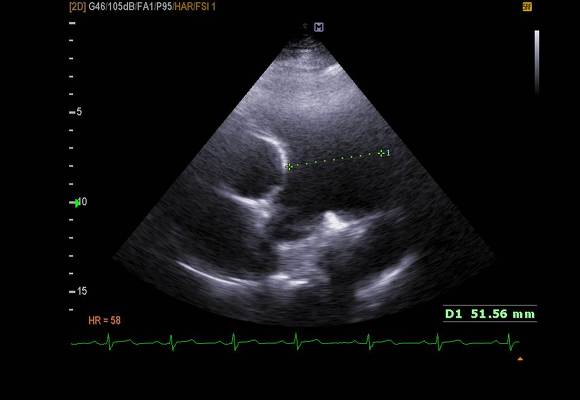

pic 8. main Pulmonary Artery - 51mm